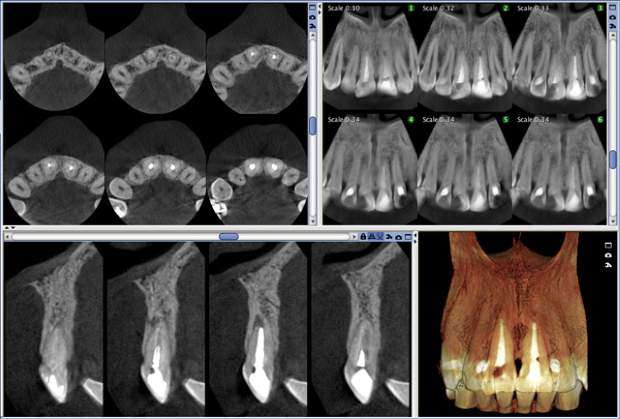

Digitale Volumentomographie (DVT) ist eine Röntgen- Bildgebungstechnologie, bei der auf einer Kreisbahn einzelne Projektionsaufnahmen eines Patienten aus unterschiedlichen Winkeln aufgenommen werden. Ein volumetrisches 3D-Bild der abgebildeten Region wird aus diesen 2D-Projektionen errechnet. Die daraus resultierende isometrische Ortsauflösung im Volumen kann mit unserem fortschrittlichen Bildbearbeitungsprogramm aus jedem Winkel in der axialen, koronalen und sagittalen Querschnittsebene betrachtet werden.